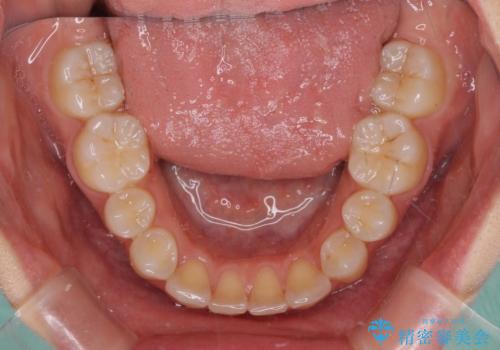

抜歯矯正を行ったことで、デコボコが改善されただけでなく、口元も下がったことで口が閉じやすくなりました。